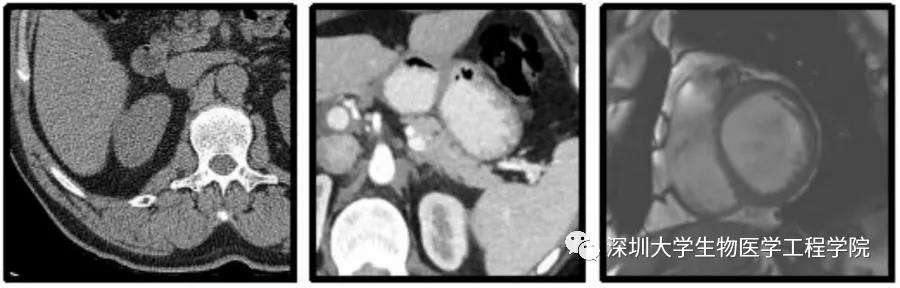

最近,腾讯防水墙上线了一种由黑白灰图片构成的验证码,乍一看,它们缺乏美感,略显沉闷、单调。

临床上有许多色彩单一、形状难辨的图片,蕴含着关于人类身体与疾病的生命密码,像这样的医学图像,是医学诊疗和研究的“路标”,可以提供给医生丰富的医学疾病信息。在医学上,90%的临床诊断需要借助经过标注的医学影像——病灶和相关器官的有效标注数据,能帮助医生在疾病诊断、病情评估、发展趋势预测、治疗策略制定等方面,提供重要的定量化信息。被标注的医学图像,融入了专家的经验知识与判断,能够缩减广大医务人员的重复工作和劳动时间,极大推动医学研究和临床诊疗的高效开展。

基于这个想法,深圳大学高毅教授团队和腾讯安全平台部合作研发并上线了“MedCAPTCHA 医学图像验证码”的公益实践项目。项目中,研发人员把医学院提供的未经标注的海量医学图像,以图片验证码的形式投放上线,以借助大众网民勾画的小动作,集中大力量来对这些医学图像进行勾画标注。